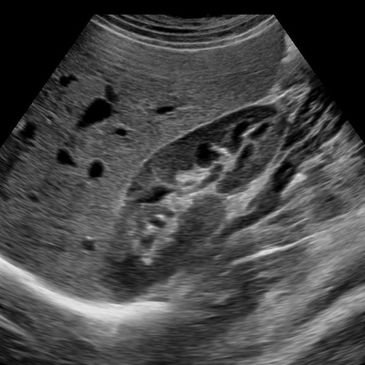

Ultrasound Scanning Guide for Abdomen and Male Pelvis

Ultrasound Scanning Guide for Obstetrics and Gynecology

Published by Wiley